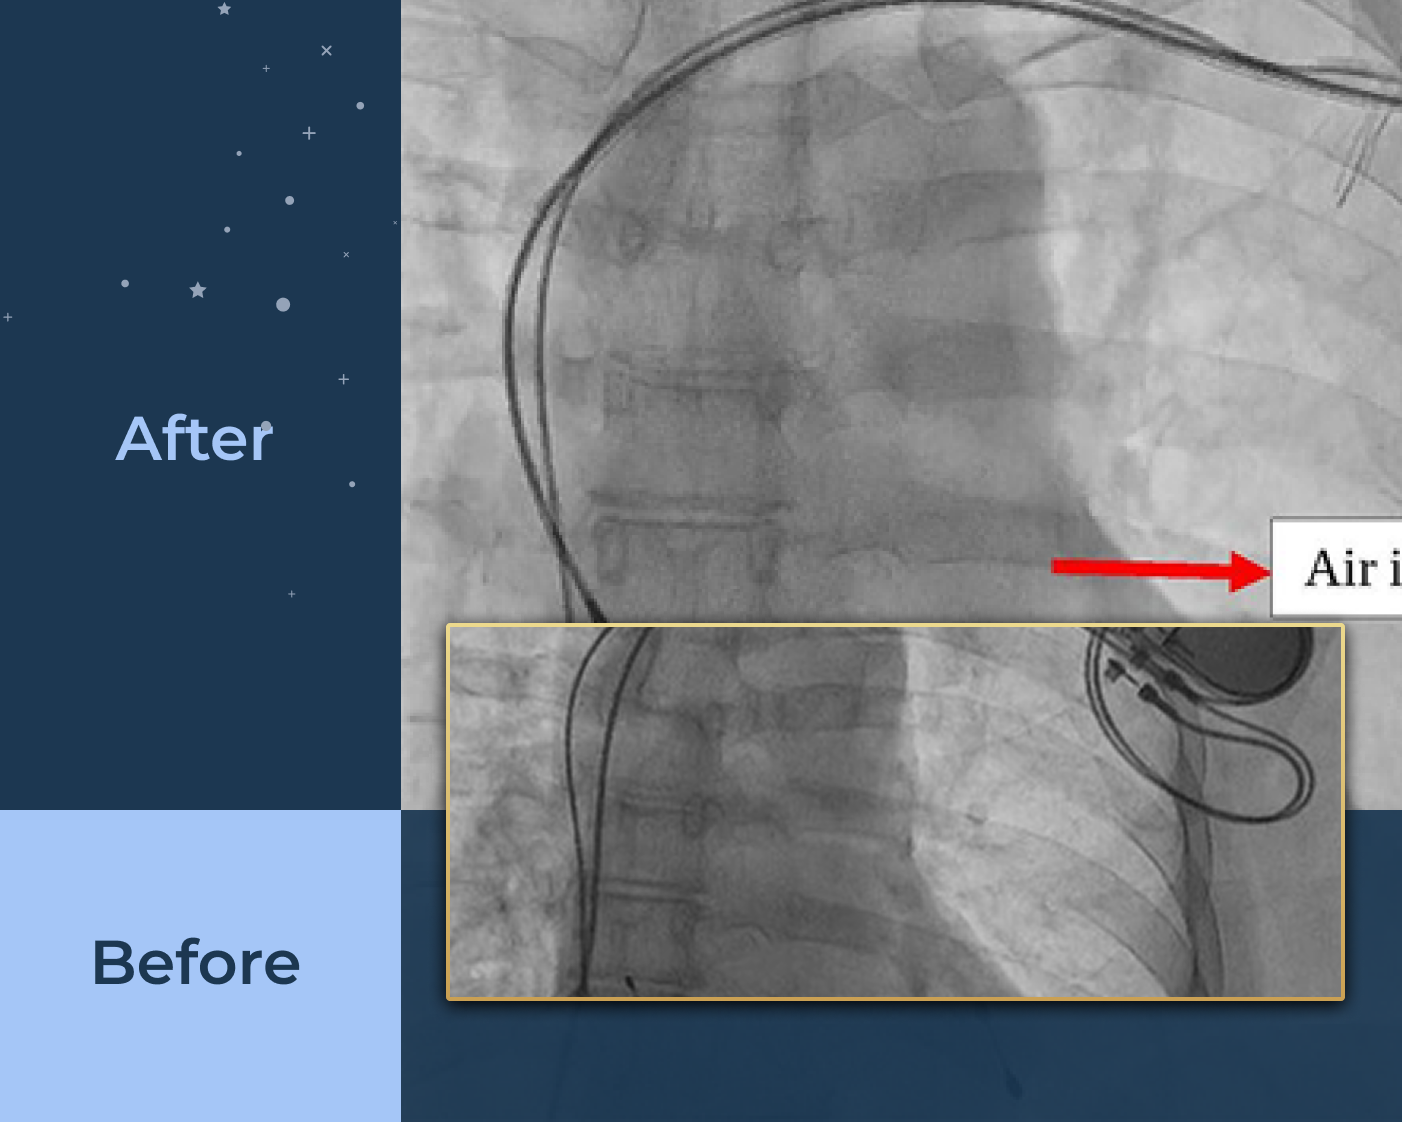

Interventions including Angiograms, Pacemaker Implantation, and Coronary Stenting.

Specialized stenting to restore blood flow with precision and monitoring for better heart function.

Specialized procedures including coronary, peripheral, and carotid stenting along with IVC filter devices.